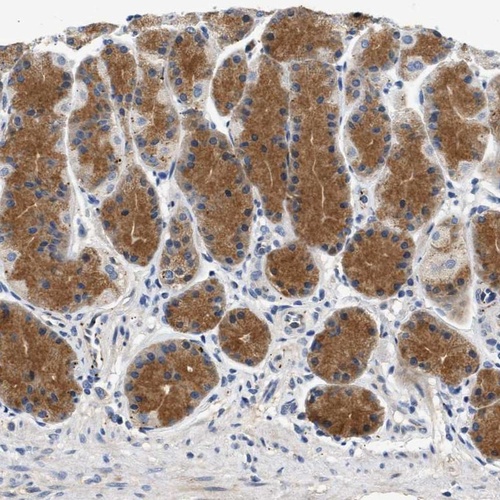

Immunohistochemical staining of human stomach shows moderate cytoplasmic positivity in glandular cells.